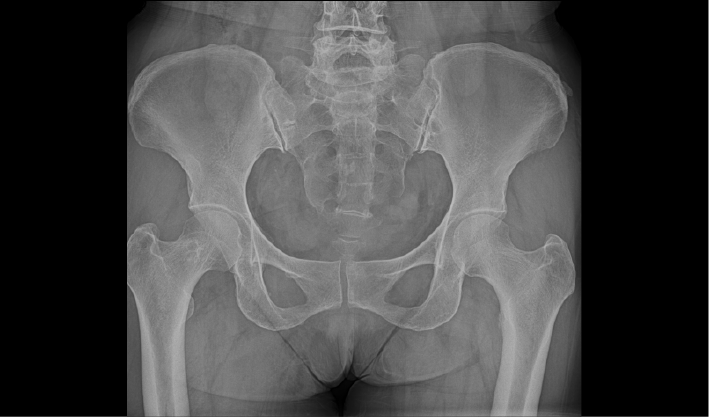

配合十軸智能全自動操控,實現六向跟蹤和一鍵自動擺位切換,融合高端配置,帶來一流的圖像,簡便操控,快捷流程,輔助醫生快速精準診斷。

消除線噪聲的同時不損失圖像細節,保持邊緣和分辨率,不會引入新偽影,增加圖像銳利度。

兩塊平板組合運用多種場景,減少平板插拔,簡化流程,提升拍攝效率。

管球無位移,消除運動誤差,提高拼接成功率。

重疊區域面積小,減少曝光次數,減少輻射劑量。

AEC自動曝光和影像均衡算法,保證拼接圖像統一亮度和對比度。